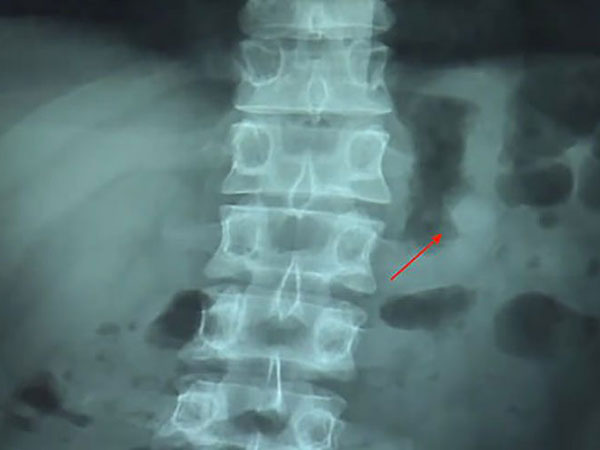

ഇത് തിരിച്ചറിഞ്ഞ ശേഷം ബെന് ഉടനേ തന്നെ ആശുപത്രിയിലേക്ക് എത്തി. പിന്നീട് അവിടുന്ന് നടത്തിയ സ്കാനിംങ്ങ് റിപ്പോര്ട്ടിലാണ് ഇത് വയറ്റിലുണ്ട് എന്ന് കണ്ടെത്തിയത്. എന്നാല് പരിഭ്രാന്തനാകാതെ ഇരിക്കുന്നതിന് വേണ്ടി തന്നെയാണ് ഇവരോട് ഡോക്ടര്മാര് ഇയാളോട് ആവശ്യപ്പെട്ടത്. പുറത്തെടുക്കാന് രണ്ട് തരത്തിലുള്ള ഓപ്ഷനും ഇദ്ദേഹത്തിന് ഡോക്ടര്മാര് നല്കിയത്.